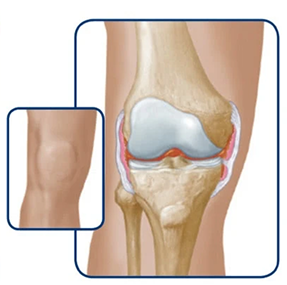

Joint bleeds—also called hemarthrosis—can happen when a joint is stressed. Repeated bleeds in the same joint may lead to chronic synovitis, where the joint lining becomes swollen and thick. Over time, this can limit movement and cause lasting joint damage.

Healthy knee

The bleed starts to enter the joint

The joint swells

If bleeds continue, it can degrade the cartilage and bone within the joint.

Over time, the joint may swell, change shape, and lose mobility.